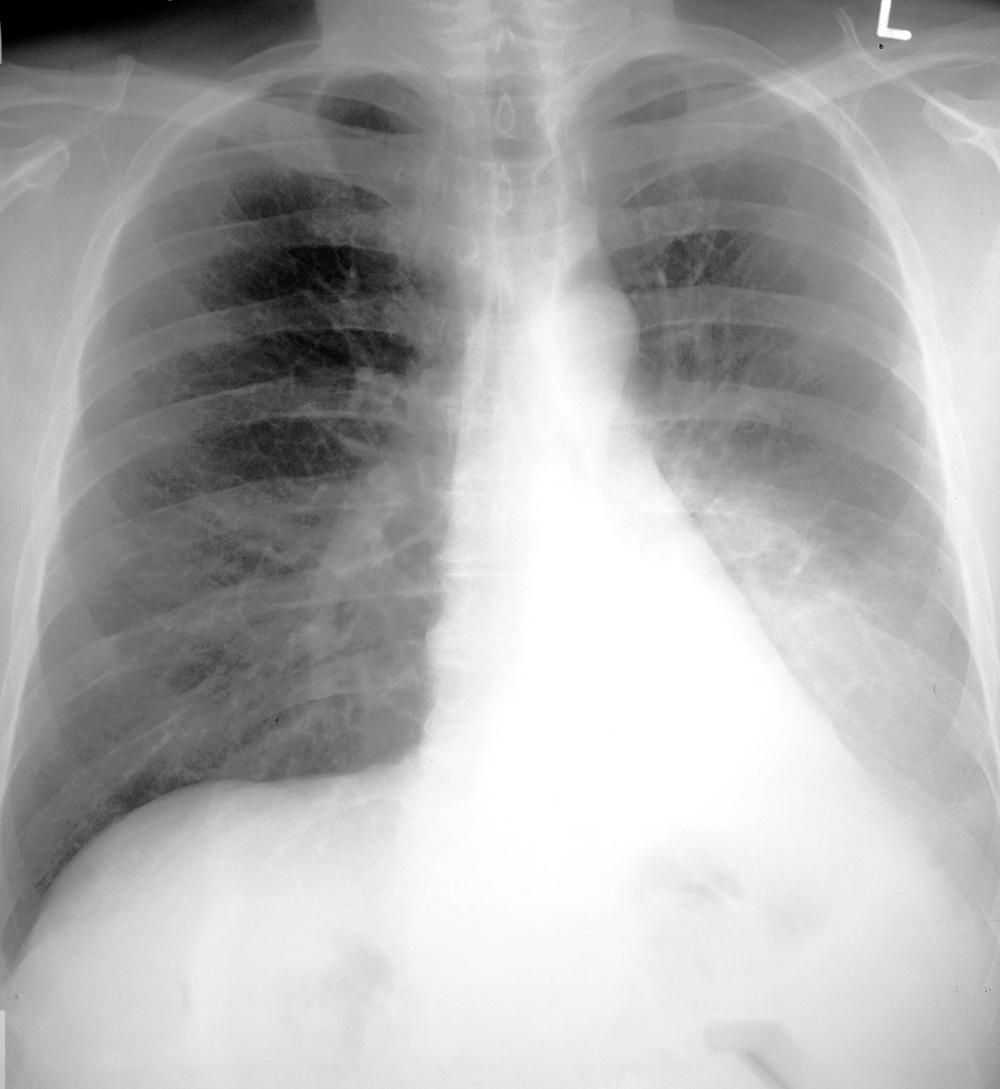

Topic 1

intermediate case PNA

Further Explanation: